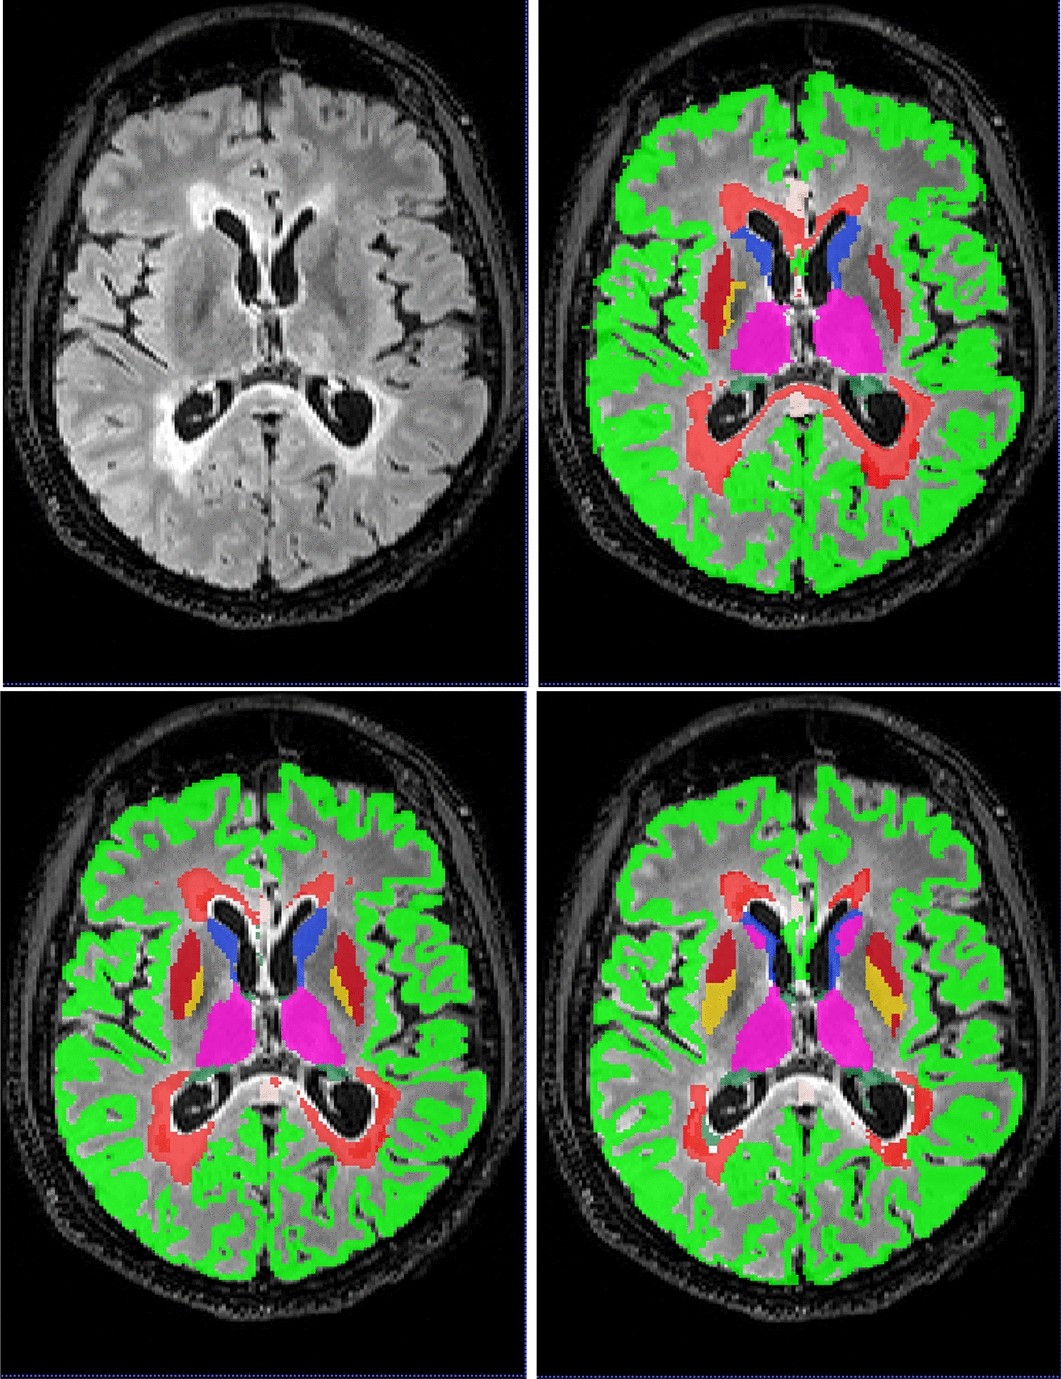

Figure 4

From: Simultaneous lesion and brain segmentation in multiple sclerosis using deep neural networks

An axial slice of case 1016SACH from the MSSEG dataset. Top left, FLAIR, top right, fused ’ground truth’, bottom left, DeepSCAN segmentation, trained on the Insel90 dataset, bottom right, nnUnet segmentation, trained on the same Insel90 dataset. nnUnet model incorrectly labels parts of Caudate nucleus as Thalamus, and incorrectly places boundary between Pallidum and Putamen.